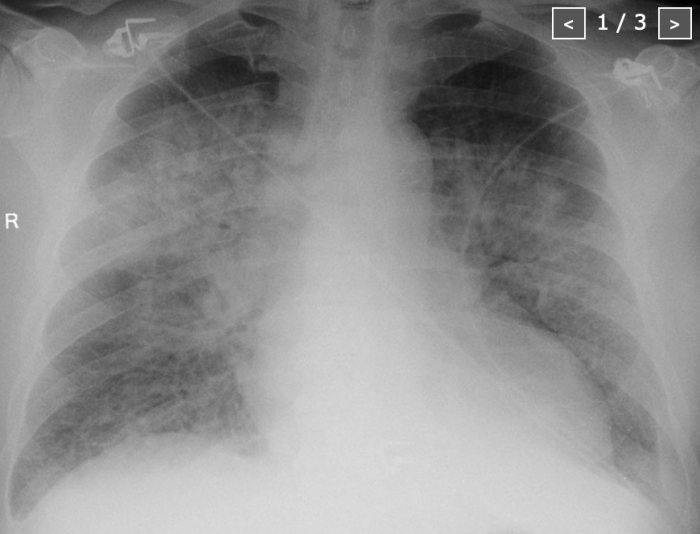

A patient is seen by the emergency team, diagnosed with a hip fracture after he slipped and fell, and admitted by the orthopedics service. His medications have been held and he has been made NPO and started on maintenance fluids in anticipation of an operation tomorrow. He is boarding in the emergency department when he wakes up with shortness of breath and hypoxia secondary pulmonary edema.

This case involves the approach to the patient with acute dyspnea. The patient is tachypneic, hypoxic, and hypertensive. The team should consider multiple possibilities but recognize pulmonary edema as the most likely cause.

Chest X-ray for the Case

Reference = https://radiologyassistant.nl/chest/chest-x-ray-heart-failure